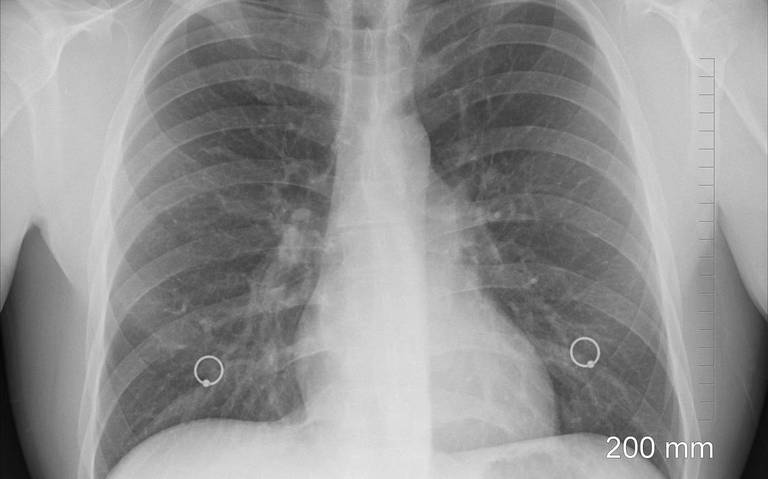

Tabasco.- En lo que va del año, se han estudiado 500 casos de Tuberculosis en Tabasco, reportó la Jurisdicción Sanitaria del municipio de Centro, por ello, ha incrementado en un 68 por ciento la búsqueda de personas que han estado en contacto con los pacientes con la enfermedad.

El jefe de la jurisdicción, Carlos de la Cruz Alcudia, expuso que diez de cada 100 casos han salido positivos, sin embargo, esto ha ido al alza porque, al momento de obtener los resultados de un paciente sospechoso, éste ya hizo contacto con más personas dispersando el virus.